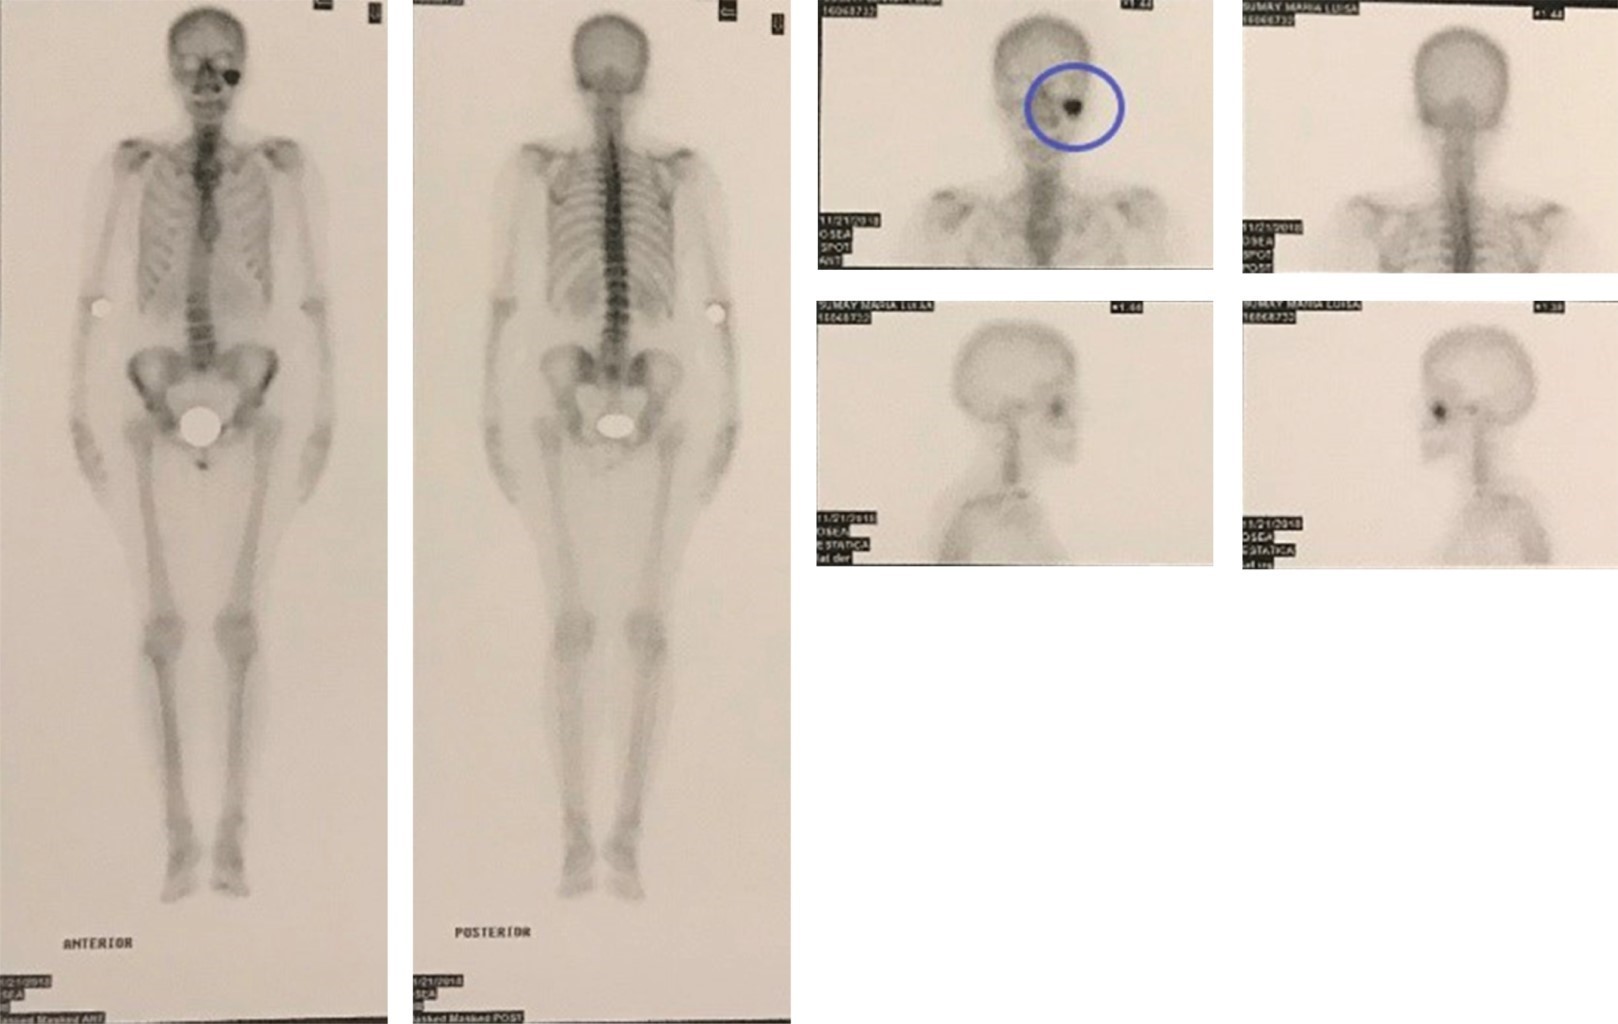

Teniendo en cuenta sus antecedentes de carcinoma de colon y para descartar la posible metástasis del tumor se solicita una centellografía total focalizada en el macizo facial, la cual muestra una hipercaptación del marcador en la apófisis coronoides del maxilar izquierdo, el resto del escáner reveló una fijación ósea del radiofármaco regular y simétrica (foco osteoblástico único) (Figura 7).

Figura 7